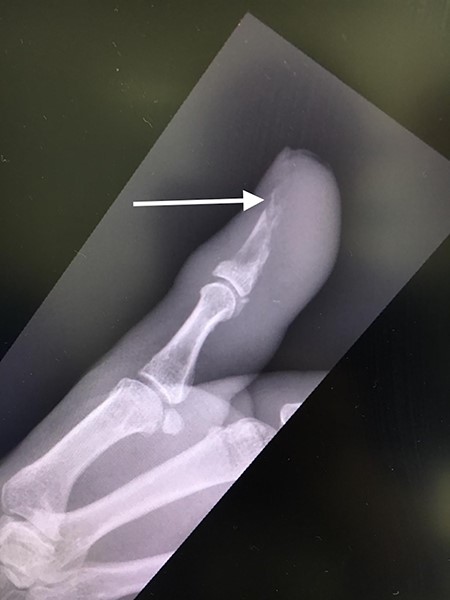

The patient was then reviewed 6 weeks after her initial presentation, following the results of the sarcoma MDT, which confirmed a benign tumour. At this point, the patient reported some tenderness around the surgical incision, but that her symptoms were improving. It was thought that she had no signs of ongoing infection in the thumb. The outcome was for monitoring of her symptoms with no indication for surgical excision. She had a follow-up X-ray in 6 weeks’ time that showed resolution of the lytic lesion (Figs 6 and 7).

AP follow-up radiograph of right thumb 6 weeks post-admission showing resolution of lytic lesion.